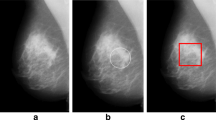

Breast cancer is the most common cancer diagnosed in women worldwide. Up to 50% of non-palpable breast cancers are detected solely through microcalcification clusters in mammograms. This article presents a novel and completely automated algorithm for the detection of microcalcification clusters in a mammogram. A multiscale 2D non-linear energy operator is proposed for enhancing the contrast between the microcalcifications and the background. Several texture, shape, intensity, and histogram of oriented gradients (HOG)–based features are used to distinguish microcalcifications from other brighter mammogram regions. A new majority class data reduction technique based on data distribution is proposed to counter data imbalance problem. The algorithm is able to achieve 100% sensitivity with 2.59, 1.78, and 0.68 average false positives per image on Digital Database for Screening Mammography (scanned film), INbreast (direct radiography) database, and PGIMER-IITKGP mammogram (direct radiography) database, respectively. Thus, it might be used as a second reader as well as a screening tool to reduce the burden on radiologists.